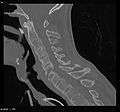

Fracture of the T5 and C7 vertebra due to trauma in a person with ankylosing spondylitis as seen on a CT scan

Prognosis is related to disease severity.[7] AS can range from mild to progressively debilitating and from medically controlled to refractory. Some cases may have times of active inflammation followed by times of remission resulting in minimal disability while others never have times of remission and have acute inflammation and pain, leading to significant disability.[7] As the disease progresses, it can cause the vertebrae and the lumbosacral joint to ossify, resulting in the fusion of the spine.[24] This places the spine in a vulnerable state because it becomes one bone, which causes it to lose its range of motion as well as putting it at risk for spinal fractures. This not only limits mobility but reduces the affected person's quality of life. Complete fusion of the spine can lead to a reduced range of motion and increased pain, as well as total joint destruction which could lead to a joint replacement.[25]

Osteoporosis is common in ankylosing spondylitis, both from chronic systemic inflammation and decreased mobility resulting from AS. Over a long-term period, osteopenia or osteoporosis of the AP spine may occur, causing eventual compression fractures and a back "hump".[26] Hyperkyphosis from ankylosing spondylitis can also lead to impairment in mobility and balance, as well as impaired peripheral vision, which increases the risk of falls which can cause fracture of already-fragile vertebrae.[26] Typical signs of progressed AS are the visible formation of syndesmophytes on X-rays and abnormal bone outgrowths similar to osteophytes affecting the spine. In compression fractures of the vertebrae, paresthesia is a complication due to the inflammation of the tissue surrounding nerves.